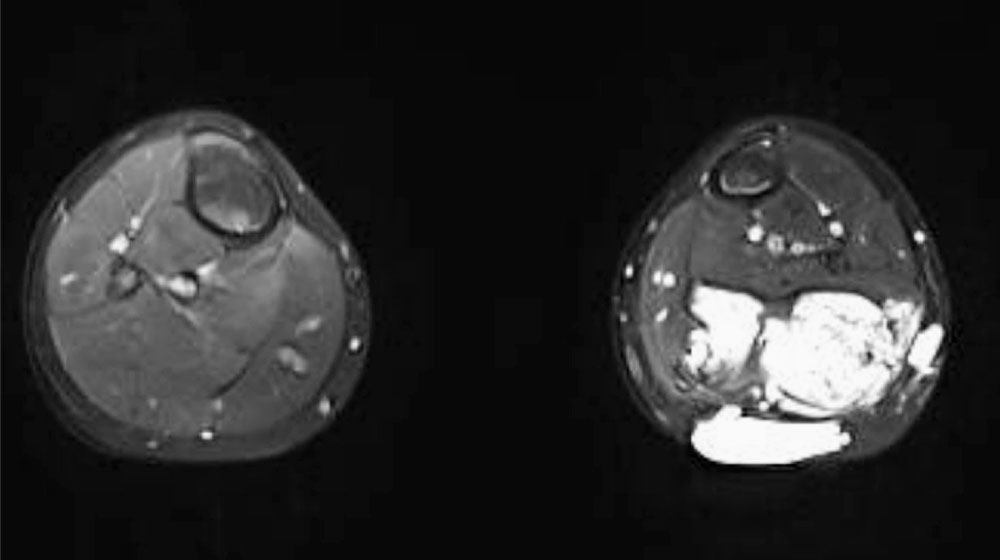

Particularly in fibro-adipose vascular anomaly (FAVA), contractures are to be expected owing to the regular constrictive connective tissue remodeling with shortening of the musculature. Most frequently, this relates to the calf muscles and a resulting pes equinus.

There is a loss of extensible muscle due to the remodeling of the existing musculature partly into connective tissue (fibrous connective tissue and fat) structures, partly interspersed with dysplastic venous vessels.

Achilles tendon lengthening should be Z-shaped and performed openly in malformation patients. Percutaneous procedures potentially carry an increased risk of bleeding because of the sometimes massive phlebectasia.

In these cases, removal of the FAVA including the affected muscle is recommended. This can be a very complex procedure if nerves and normal vessels are encased by the malformation in the knee area. However, to date this seems to be the only therapeutic approach to treat both the contracture and the other symptoms caused by FAVA.

Likewise, one or more prior sclerotherapies of the venous malformation part of FAVA preoperatively is the rule. It is obligatory to close veins communicating with the deep conducting venous system beforehand (interventional or open surgery) in order to prevent the risk of thromboembolism.